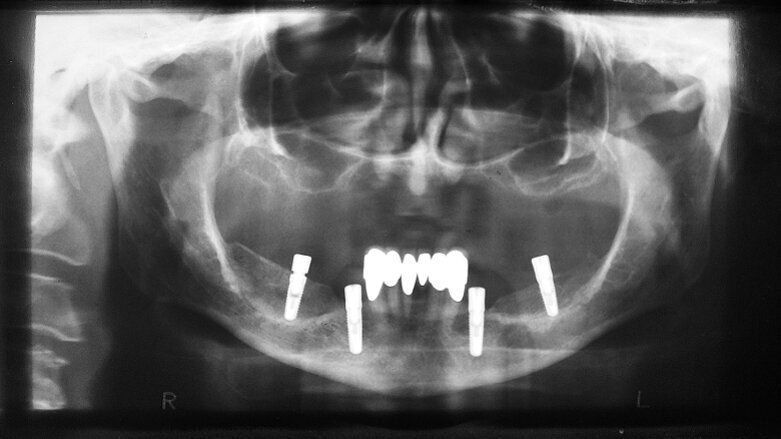

Fig. 2 : Tomographie panoramique dentaire après chirurgie d’augmentation par une greffe osseuse de crête iliaque.

La patiente n’était pas satisfaite de sa prothèse amovible mandibulaire et souhaitait une prothèse fixe. Afin de permettre un traitement par des constructions de bridges sur implants en titane ostéo-intégrés, une greffe osseuse était nécessaire dans les zones édentées de la mandibule. La patiente a été clairement informée des risques et des dangers potentiels concernant les aspects fonctionnels et esthétiques, pendant et après la période du traitement. Les étapes du traitement lui ont été expliquées. Cinq mois après la reconstruction de la crête alvéolaire par de l’os de crête iliaque (Fig. 2), nous étions en mesure de poursuivre le plan de traitement qui comprenait la planification prothétique préopératoire et la navigation implantaire.

Deux petits lambeaux de pleine épaisseur ont également été décollés afin d’éliminer la vis d’ostéosynthèse utilisée pour stabiliser la greffe osseuse autologue de la chirurgie d’augmentation précédente (Fig. 9). L’insertion des implants a été réalisée à l’aide d’une clé à cliquet DRM et d’une douille standard, avec un couple de serrage prédéfini de 35–45 Ncm, afin de parvenir à une stabilité primaire maximale. Les façonneurs gingivaux ont été insérés avec un couple de serrage de 20 Ncm (Fig. 10) et, après l’insertion des implants, les lambeaux ont été suturés au moyen de fils non résorbables (Prolene 5/0). Les sutures ont été retirées après sept jours. Une tomographie panoramique dentaire postopératoire a permis de visualiser les implants insérés dans la mandibule. Les zones d’augmentation osseuse étaient également clairement reconnaissables sur les deux cotés (Fig. 11).